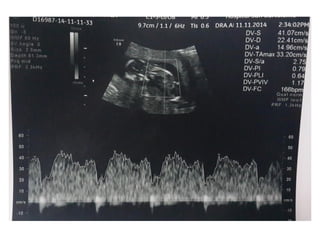

VALORACIÓN DV

• Semanas 11+0-13+6 y la LCC entre 45-84 mm. El feto no

debe moverse.

• El tamaño de la imagen debe ser tal que el tórax y abdomen

fetal ocupen toda la pantalla. Se debe obtener un corte

sagital medio del tronco fetal.

• Se debe usar el Doppler color para demostrar la vena

umbilical, el ductus venoso y el corazón fetal. La ventana

del Doppler pulsado debe ser pequeña (0,5-1,0 mm) y debe

situarse en la zona de aliasing normalmente en amarillo

• El ángulo de insonación debe ser menor de 30 grados.

• El filtro debe ser de baja frecuencia (50-70 Hz), para

permitir la visualización de la onda completa.

• La velocidad de barrido debe ser alta (2-3 cm/s), para

obtener una forma más ancha y poder evaluar mejor la onda

A.